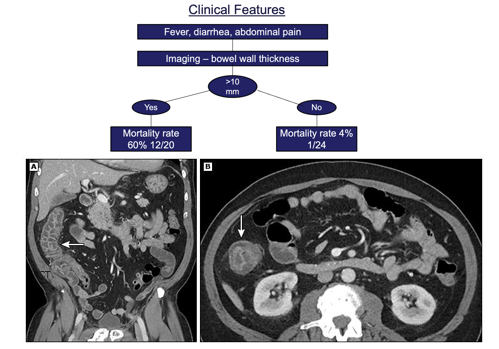

Neutropenic Enterocolitis (Typhlitis)

Key features:

• Fever, abdominal pain, diarrhea

• RLQ tenderness

• CT: Bowel wall thickening

Management:

• Broad-spectrum antibiotics including anaerobes

• Bowel rest, NG suction if obstruction

• Surgery only for perforation/hemorrhage